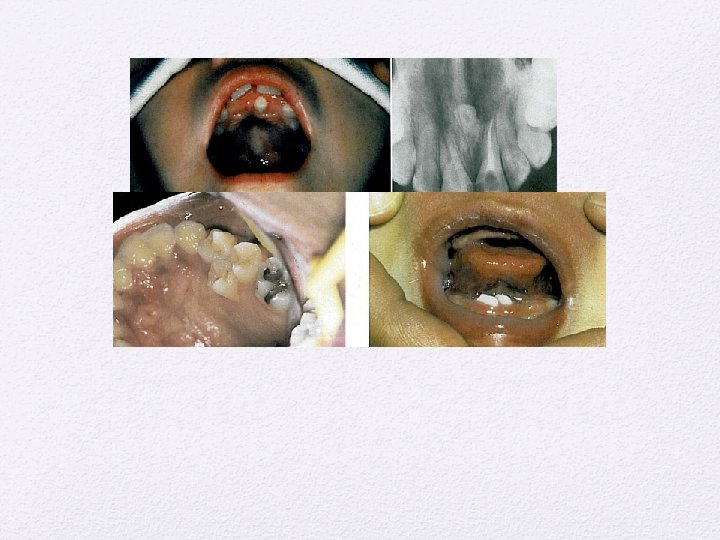

Kista Odontogenik • Kista periapikal • Kista Dentigerous • Kista erupsi • Kist Paradental • Odontogenik keratocyst • Kista lateral periodontal • Kista ginggiva • Kista dental lamina • Kista Glandular odontogenik

Lesi Periapikal • Periodontitis apikalis kronis • Granuloma periapikal • Kista periapikal • Abses periapikal